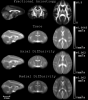

DTI-TEMPLATE-RHESUS-MACAQUES

DTI-TEMPLATE-RHESUS-MACAQUES Images

3 Images available.